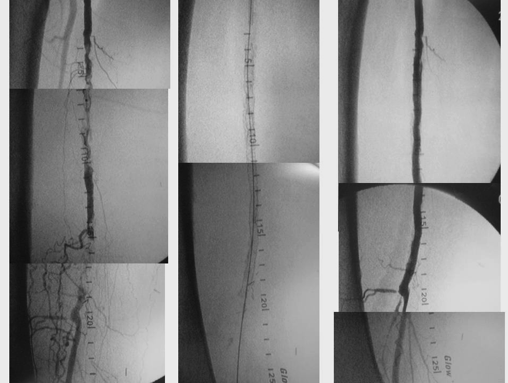

Recanalización Endovascular Compleja mediante Stent en paciente portador de by-pass digital